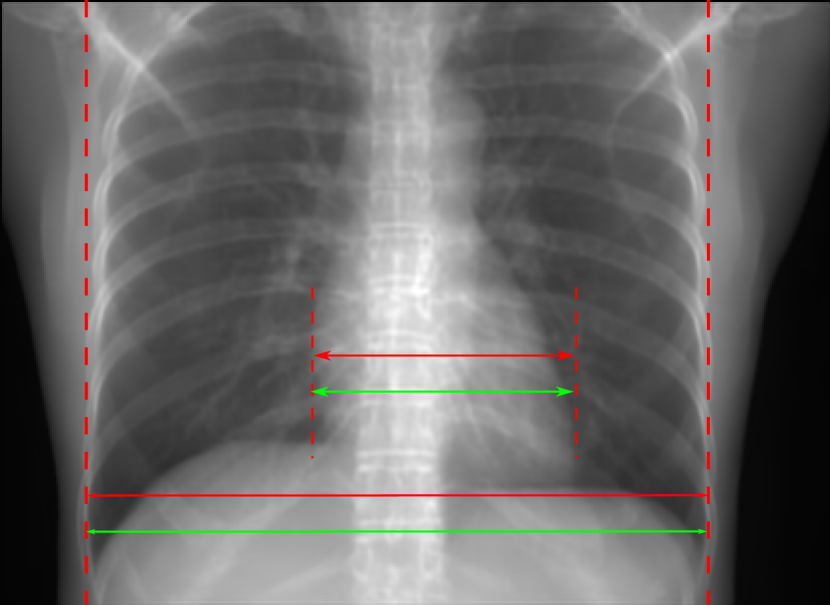

Figure 10: Perspective deformation learning in one exemplary patient case for chest X-ray imaging. The maximal horizontal cardiac diameter and the maximal horizontal thoracic diameter in (b) and (d)-(f) are indicated by the horizontal red lines, while those in the reference image (a) are green lines. The cardiothoracic ratio, RMSE, and SSIM for each image is displayed in its corresponding subcaption.

TABLE II: Quantitative evaluation of different methods on chest data.

Method Metric 0superscript00^{\circ} input 0superscript00^{\circ} 0&180superscript0superscript1800^{\circ}\&180^{\circ} 0&180superscript0superscript1800^{\circ}\&180^{\circ}

perspective Cart. Cart. polar

Pix2pix RMSE 18.68 11.88 7.90 4.98

GAN SSIM 0.6401 0.8103 0.8944 0.9493

Trans RMSE 18.68 17.21 12.12 13.06

U-Net SSIM 0.6401 0.7744 0.8950 0.8899

The results of one patient in chest X-ray imaging are displayed in Fig. 10, where the cardiothoracic ratio is assessed as an exemplary clinical application [32]. In the reference image (Fig. 10(a)), the maximal horizontal cardiac diameter (MHCD) and the maximal horizontal thoracic diameter (MHTD) are indicated by two green horizontal lines. Its cardiothoracic ratio is 0.4237. In the 0superscript00^{\circ} perspective projection image (Fig. 10(b)), all the anatomical structures can be visualized with fine resolution. However, due to perspective deformation, anatomical structures, e.g. the ribs and the spine, are deformed. The deformations are visualized better in the difference image Fig. 10(c). Compared with the ribs and the spine, the heart has less deformation as its location is closer to the isocenter. In Fig. 10(b), the MHCD and the MHTD are indicated by two red horizontal lines, while the green lines are those of the reference image. While the MHCD has changed little from 10.47 cm to 10.16 cm, the MHTD has changed considerably from 24.71 cm to 25.40 cm. As a consequence, the cardiothoracic ratio becomes 0.4002, which is below the normal range of 0.42 - 0.50 [32]. The result of learning perspective deformation from 0superscript00^{\circ} single view is displayed in Fig. 10(d), where the MHCD and the MHTD are 10.63 cm and 24.71 cm, respectively. The MHTD of Fig. 10(d) is the same as that of the reference image. This is also reflected by the difference image Fig. 10(g), where the lower ribs have small errors. However, the upper ribs as well as the spine still have considerable errors. The results of perspective deformation learning from 0&180superscript0superscript1800^{\circ}\&180^{\circ} views in Cartesian and polar coordinates are displayed in Fig. 10(e) and Fig. 10(f), respectively. The measured MHCDs and MHTDs in these two images are very close to the reference ones. Hence, their cardiothoracic ratios, 0.4214 and 0.4240 respectively, are close to the reference ratio as well. In the difference images (Fig. 10(h) and Fig. 10(i)), the errors of ribs and spine decrease as their boundaries are no longer apparently visible. Nevertheless, Fig. 10(i) has less error than Fig. 10(h), achieving the smallest RMSE value of 3.83. The quantitative evaluation of all the 162 testing datasets is displayed in Tab. II, where learning perspective deformation from two complementary views in polar coordinates achieves the least RMSE 4.98 and highest SSIM 0.9517, demonstrating the superiority of learning perspective deformation from two complementary views in polar coordinates.

The TransU-Net results are displayed in Figs. 10(j)-(l). Compared with their corresponding Pix2pixGAN results, the TransU-Net prediction images are more blurry, although the same perceptual loss is used. The error images in Figs. 10(m)-(o) indicate that TransU-Net reduces perspective deformation better with complementary views than a single view. The quantitative evaluation in Tab. II shows that TransU-Net cannot effectively reduce perspective deformation with a single view. With complementary views in both Cartesian and polar coordinate systems, TransU-Net achieves comparable performance, which is still considerably worse than that of Pix2pixGAN. The inferior performance of TransU-Net to Pix2pixGAN on the chest data is potentially caused by the repetitive nature of the segmental rib anatomy, which leads TransU-Net to be ineffective in extracting position-dependent features.